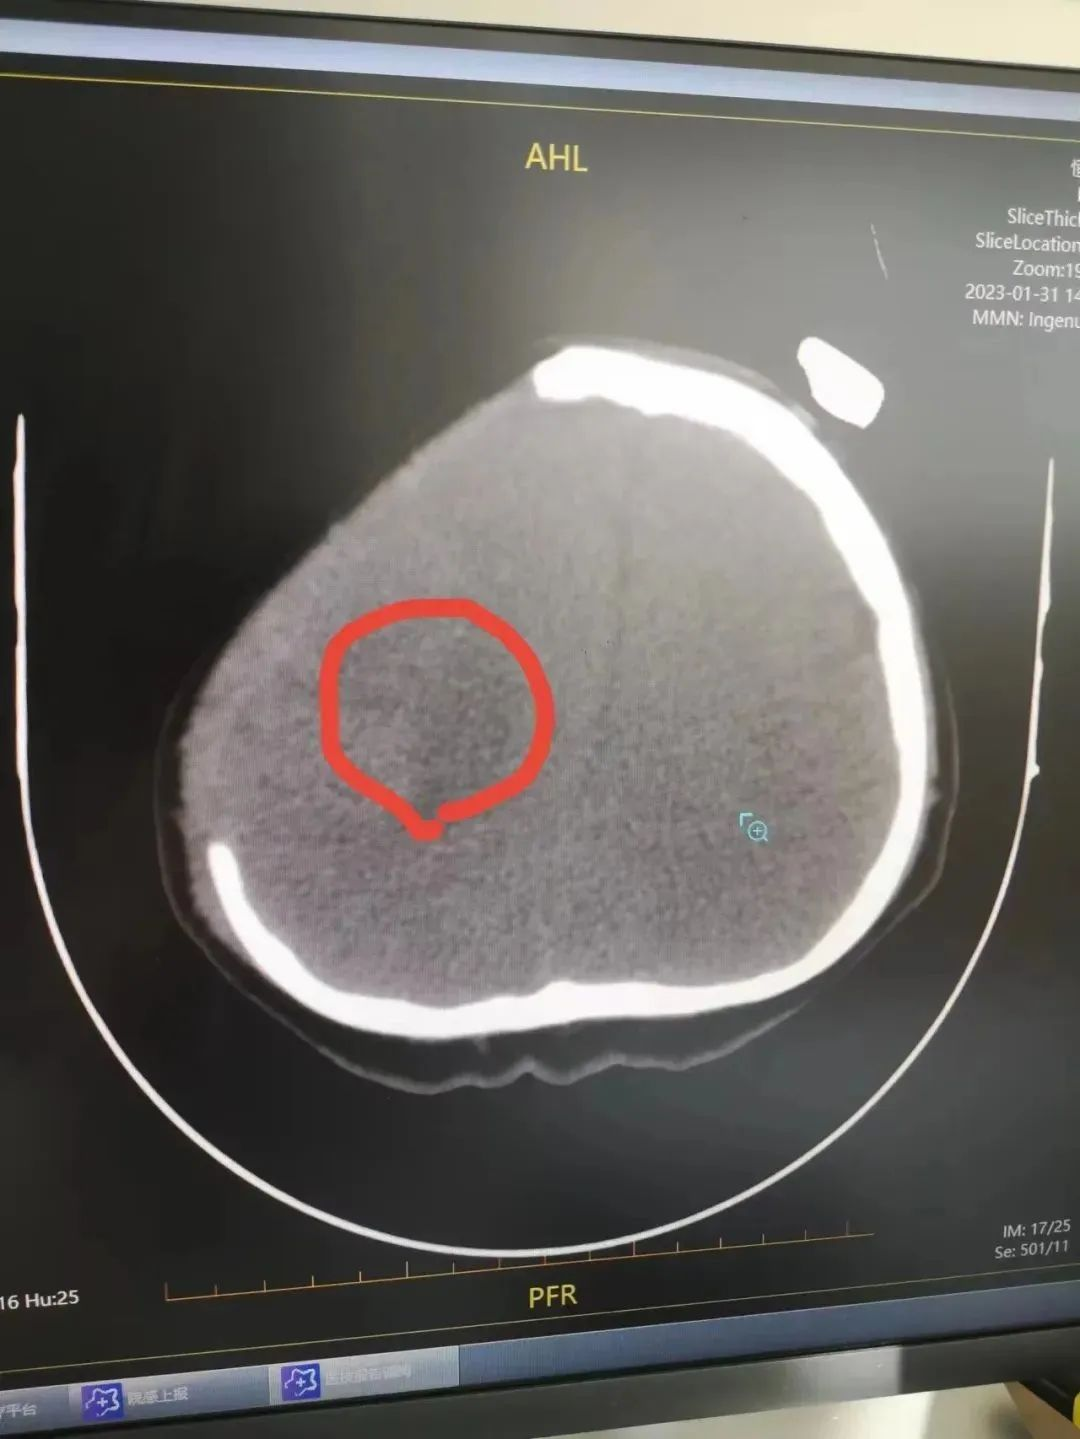

小李被送往外院抢救室后,颅脑CT提示——

右侧基底节区血肿并破入脑室,中线结构左移约17mm,考虑脑疝形成。

患者头部CT影像检查,红圈位置为出血部位

医生表示患者突发脑溢血